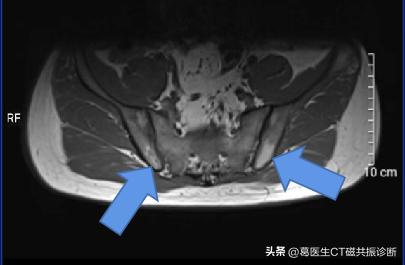

当地临床医生怀疑强直性脊柱炎,然后让患者做了骶髂关节MRI(磁共振检查),目的是评估骶髂关节是否受累。患者影像资料如图

箭号所指白色区域

因为,磁共振图像中,箭号所指区域(也就是被认为是病灶的地方)为 正常结构,专业上叫 黄骨髓

人的骨头中有红骨髓和黄骨髓,看到图中蓝色箭号为黄骨髓,由于黄骨髓中脂肪含量比较多,磁共振T1序列上表现为 高信号(偏白色)。